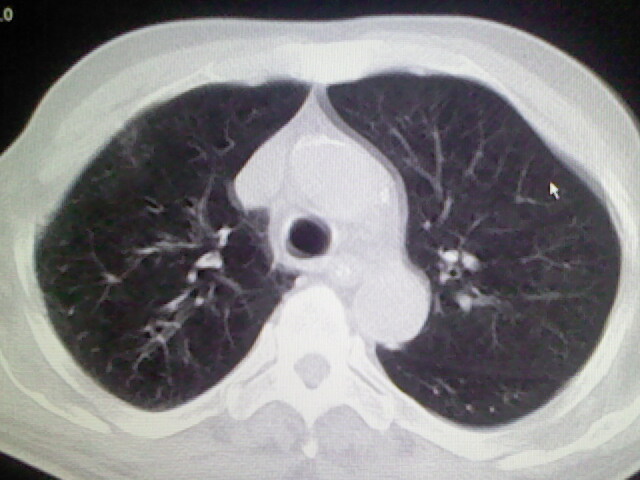

男,70岁,脑出血,长期卧床,左侧背部可触及肿块

右肺病灶考虑炎症性。

右肺病灶考虑炎症性

考虑右肺及左肺下叶炎症。

右肺及左肺下叶炎症。

考虑右肺及左肺下叶慢性炎症。

右侧肺部见片状密度增高影,边缘模糊。考虑炎症。另食管壁增厚。

右肺上叶前段病呈楔形,其尖端指向肺门,考虑肺动脉栓塞可能性大.